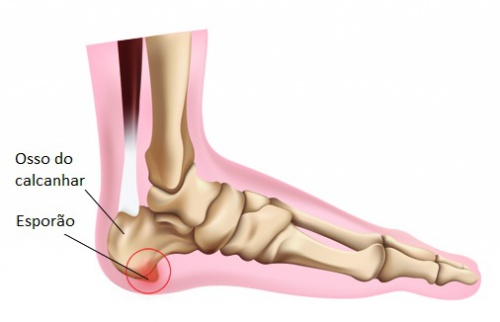

Sabe aquele esporão que insiste em aparecer no seu calcanhar? Pois é, ele é uma calcificação que surge no osso, bem na parte de baixo do calcâneo (o osso do seu calcanhar). Pensa nele como um pequeno “bico” de osso que se forma. Ele aparece justamente ali porque é um ponto de muita pressão e tensão na nossa pisada. A faixa de tecido que liga o calcanhar aos dedos, a fáscia plantar, sofre um estresse constante, e o corpo, na tentativa de proteger, cria essa estrutura óssea.

O mais importante é entender que nem sempre o esporão causa dor. A dor que você sente é, na verdade, uma inflamação na fáscia plantar. O esporão é só uma consequência. Mas quando a dor aparece, ela costuma ser mais forte pela manhã, ao dar os primeiros passos, ou depois de ficar um tempo sentada e levantar. O alívio nem sempre é imediato, mas com os cuidados certos, dá pra controlar e viver sem esse incômodo. Vamos cuidar desse calcanhar!

Essa dor nada mais é do que uma inflamação na fáscia plantar, que é aquele tecido que liga o calcanhar aos dedos do pé. O esporão em si é um depósito de cálcio que se forma nessa região. Com o tempo, ele pode irritar os tecidos ao redor, causando esse desconforto.